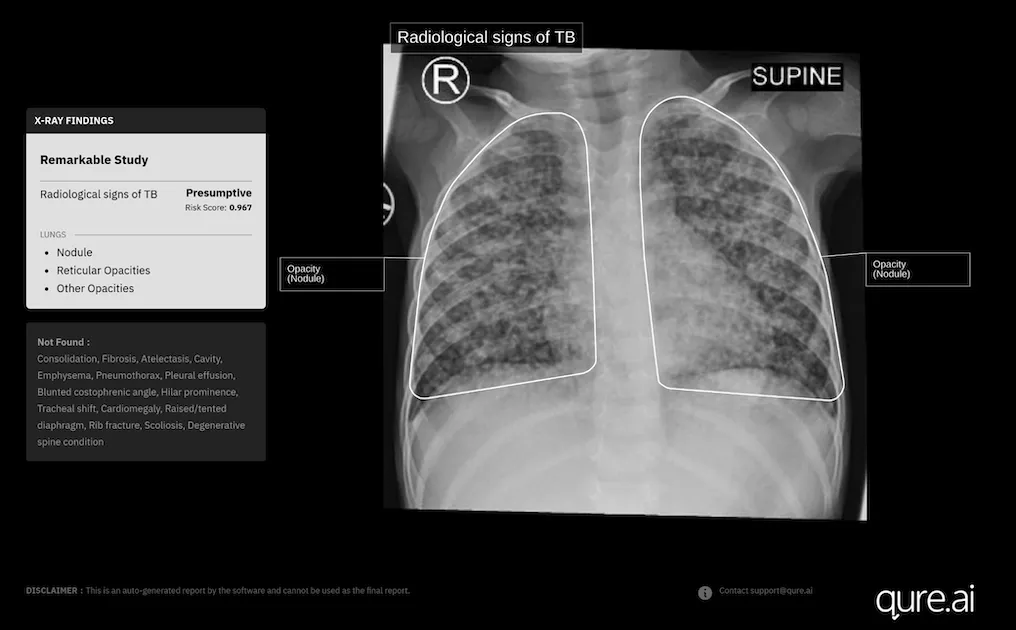

Photo courtesy of Qure.ai

It has recently received a new CE Mark under the European Union's Medical Device Regulation for the use of its AI-powered chest X-ray software, qXR, in children aged 0-3 years.

Last year, Qure.ai further trained qXR with more paediatric data – chest X-rays from children aged 0-15 years paired with corresponding GeneXpert results collected from several high TB-burden countries.

"We gathered thousands of these X-rays and retrained the model to capture the subtle and often non-specific patterns seen in younger children, particularly those under five," Divya Gupta, Chief Business Officer – Global Health at Qure.ai, told Mobihealth News in an email interview.

"Preliminary analyses from earlier test sets have already shown a 20% improvement in diagnostic accuracy against GeneXpert results after incorporating paediatric data into the model," Gupta added.